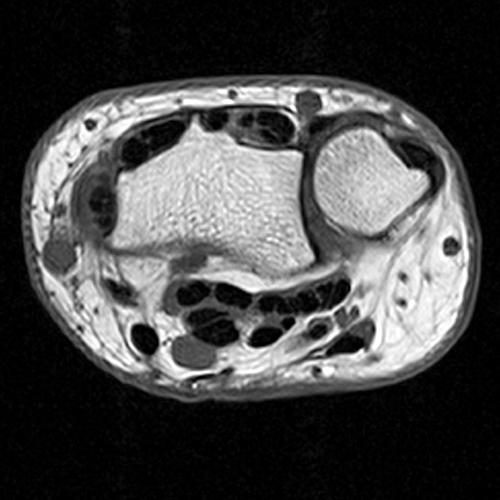

Clinical History: A 68-year-old female presents with radial-sided pain and swelling. Axial T1-weighted (1A), axial fat-suppressed proton density-weighted (1B), and coronal fat-suppressed proton density-weighted (1C) images are provided. What are the findings? What is your diagnosis?

Figure 2: The axial T1-weighted (2A), axial fat-suppressed proton density-weighted (2B), and coronal fat-suppressed proton density-weighted (2C) images demonstrate a thickened extensor retinaculum, surrounding soft tissue edema, and fluid signal in the first extensor compartment of the wrist (arrowheads). Marrow edema is noted within the subjacent radius (asterisks). A single extensor pollicis brevis and two abductor pollicis longus tendon slips are present with heterogeneous intrinsic signal.